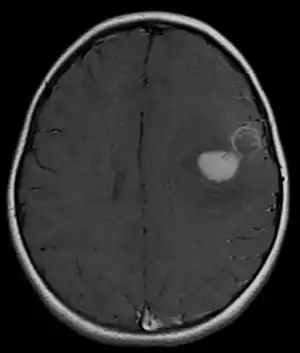

| Micrograph of an H&E stained section of a peripheral PNET. | |